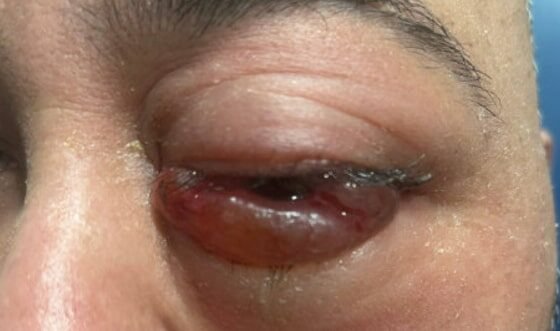

A Case Report of Invasive Mucormycosis in a COVID-19 Positive and Newly-Diagnosed Diabetic Patient